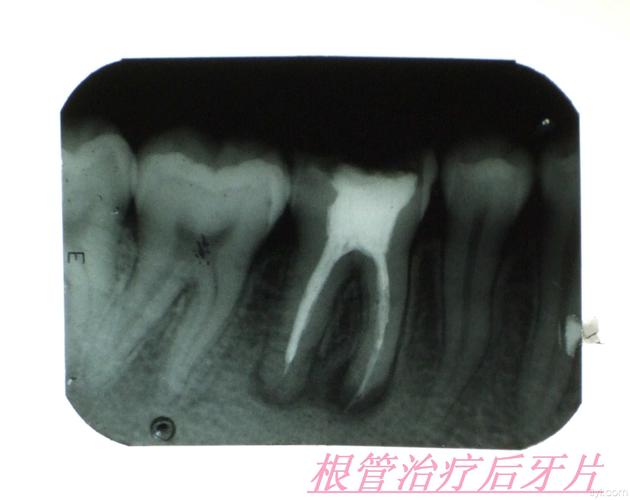

根管治疗小牙片

根管治疗小牙片,根管治疗的根管图片

根管治疗前后牙片,求助!

一年前做完根管治疗之后顺便拍了一张牙片